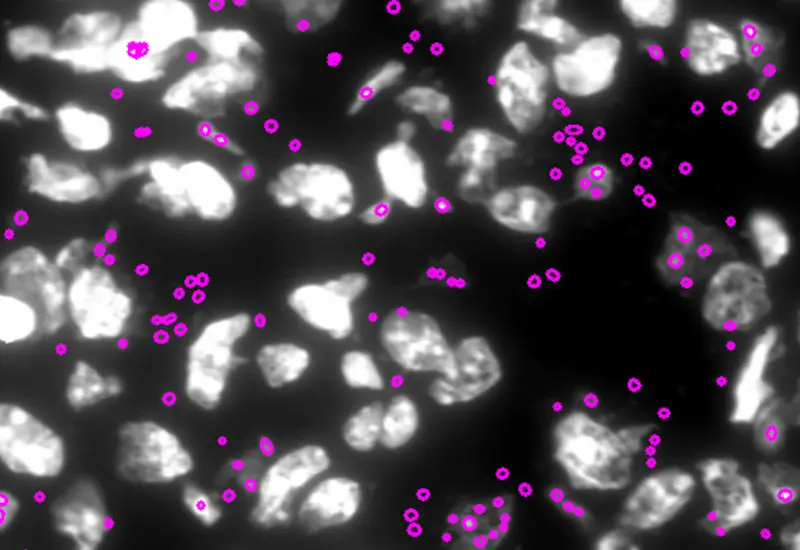

The StrataQuest contextual image analysis software was fundamental to the feasibility of this investigation. It enabled single-cell analysis, the analysis of co-expression of IDO1 and PDL1, and detection of the intracellular leishmaniasis parasite. 9

Quantification of IDO1, PD-L1, CD3 Amastin, and CD68 was performed using StrataQuest Analysis Software, which segmented nuclei based on the signal from the DAPI channel and then built and expanded a mask over staining of IDO-1/ PD-L1.

There is a great variety of streamlined analysis solutions StrataQuest Apps - available, which can be used for automated analysis. The vast potential of StrataQuest can be explored with the StrataQuest Apps . The IF Leishmaniasis APP detects intracellular Leishmania parasites based on DAPI staining and segments them in the detected host cells. 10 The number of parasites per cell is determined, and living and dead parasites can be distinguished (live/dead assays). The IF Dots APP enables the analysis of FISH-stained leishmaniasis parasites.